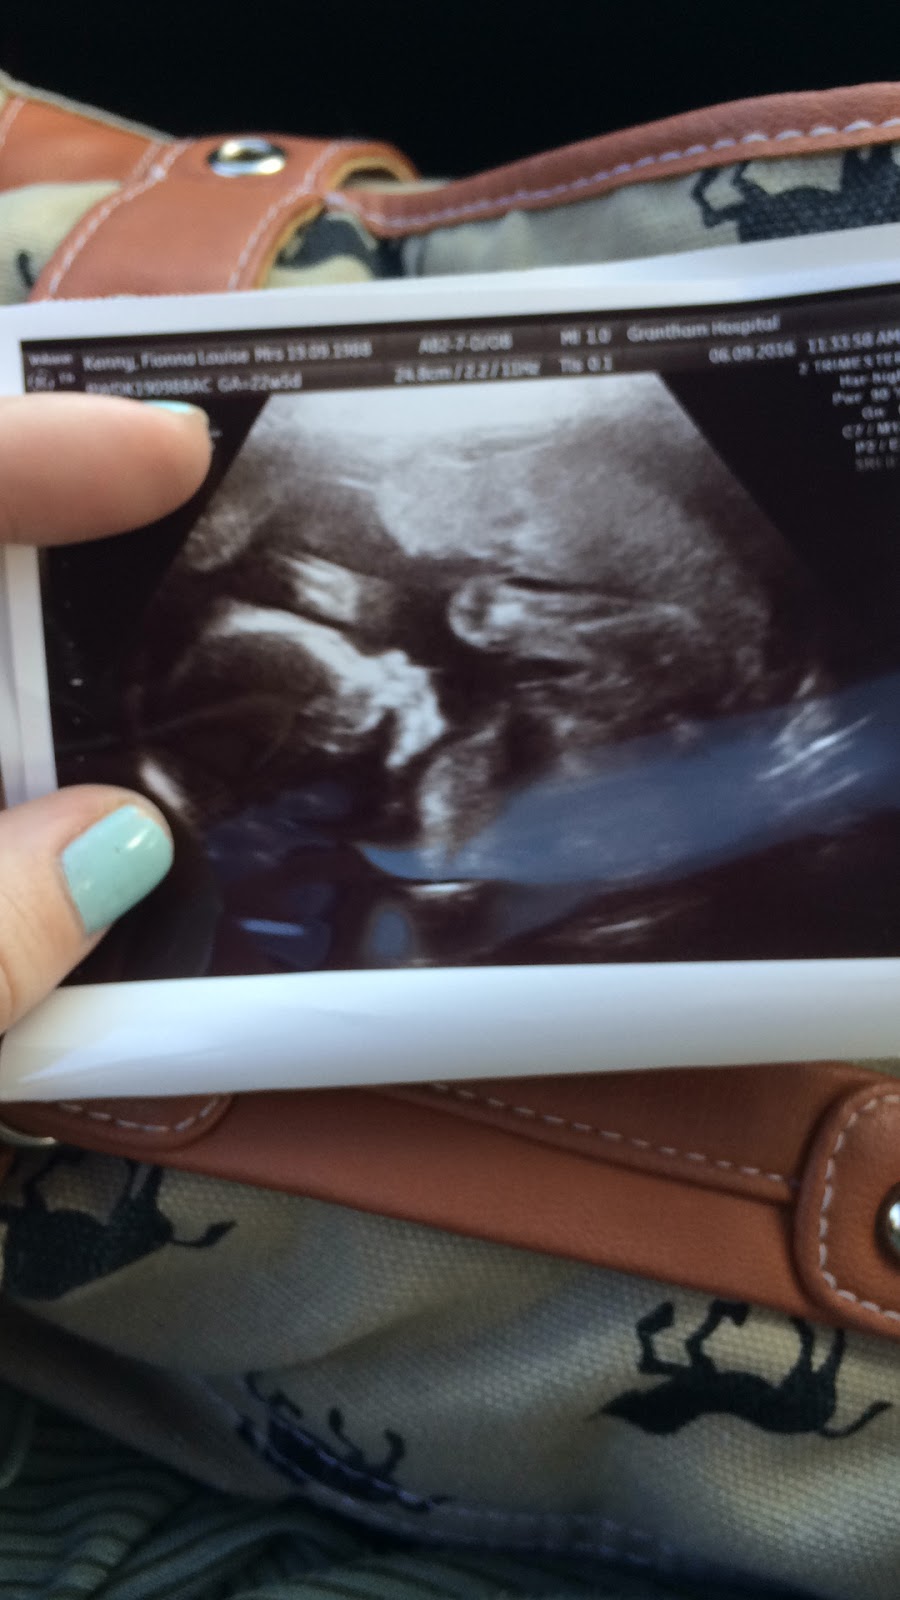

My lovely daughter Fionna is expecting a little girl..i know not everyone wants to know but they did and thats their choice.

Fionna has had to have a few scans to check as the baby wouldn't co-operate and they couldn't get a clear scan of the heart..but they have now and all is fine.

So little one is good and so is mum..she is swelling well as they say and the baby is quite a biggie .

A little pic of her ..